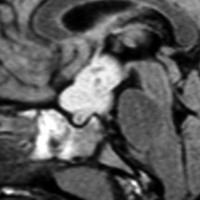

幼児の視路の毛様粘液性星細胞腫です。T2強調画像(左側)で白く高信号に写るのが特徴です。ガドリニウム増強ではまだらになっていますが,均一に真っ白に高信号になることも多いです。乳幼児のものは,ドロドロに柔らかい腫瘍です。

乳幼児時期には,病理組織像が毛様粘液性星細胞腫で,MRI T2で均一な高信号になりガドリニウムで強く増強されます。腫瘍の増大速度は速く,稀には髄液播種することもありそれが腫瘍死の原因となることもあります。奏効率の高い化学療法を早く開始する必要があります。

化学療法が有効なのは,上の画像のようにガドリニウム増強で強く増強されるタイプです,またT2強調画像で強い高信号になるものほど化学療法が有効です,要するに毛様粘液性星細胞腫の要素に化学療法が有効であるということです

この毛様細胞性星細胞腫はガドリニウムでほとんど増強されません(右側のMRI)から,化学療法を行っても小さくなりませんので,手術摘出する必要があります,実際に視床下部から発生したもの視交叉が犯されておらず,手術亜全摘出できました